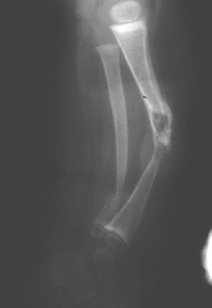

Even before fracture, 1 or both of the following signs may be evident:

-

Cyst formation and sclerosis in the lesion

Local tapering (Fig. 2)

Fig. 2. Lateral radiograph of the tibia showing the tapering and cyst formation typical of congenital pseudarthrosis.